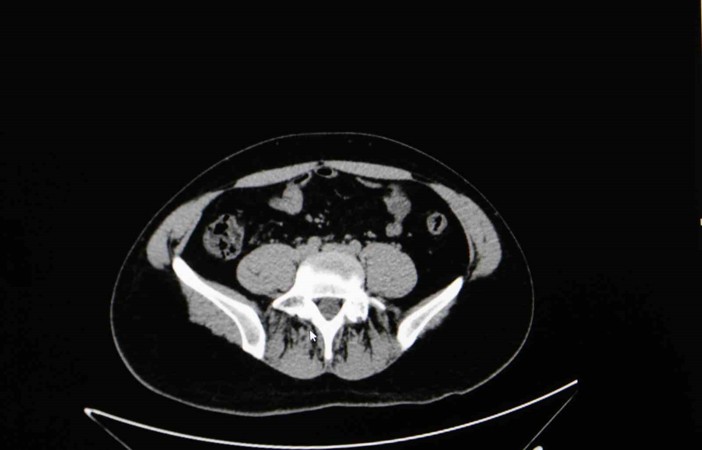

Diyarbakır Dicle Memorial Hastanesi’nde görev yapan Üroloji Uzmanı Op. Dr. Birgi Ercili “Sistit, aslında idrar torbası dediğimiz mesanenin iltihabıdır. Daha çok enfeksiyon sebepleriyle oluşur. Sistin daha çok sebebi idrar yoluna genital bölgeden ulaşan mikroorganizmalardır. Özellikle kadınlarda sistit dediğimiz durum çok fazla görülür. Çünkü kadınlarda üretra dediğimiz idrar yolu, erkeklere göre oldukça kısadır. Vajina ve anüse yakın olduğu için oradan gelen mikroorganizmaların idrar yolu aracılığıyla mesaneye ulaşması daha kolaydır. Kadınların yarısı hayatlarında muhakkak en az bir defa bu hastalığı geçirmektedir” ifadelerine yer verdi.